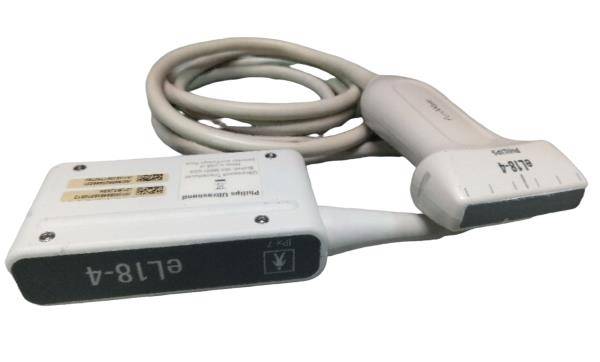

Explore the dependable and sophisticated GE Portable Logiq Book Ultrasound equipped with E8C-RS OB/GYN and 3C-RS Abdominal Transducers. Condition: Gently used with signs of cosmetic wear, yet remains fully operational for accurate diagnostics. Ideal for medical professionals seeking precision with a well-maintained machine. Brand: GE, Model: LOGIQ BOOK. Click to view our detailed listing and invest in advanced medical technology.